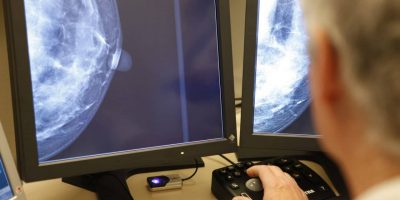

- ALIA Health, spin-off de TecSalud, y ÜMA Tech IA, Partner de Servicios de Google Cloud para el sector salud en Latinoamérica, desarrollan ALIA Health Risk Platform, una plataforma basada en inteligencia artificial que permite anticipar el riesgo de cáncer de mama a partir de mamografías.

En un contexto donde la mortalidad por cáncer de mama en México ha alcanzado uno de sus niveles más altos en décadas —con una tasa de 19.8 defunciones por cada 100 mil mujeres—, ALIA Health y ÜMA Tech IA anunciaron el desarrollo conjunto de ALIA Health Risk Platform, una plataforma basada en inteligencia artificial orientada a la predicción y estratificación del riesgo de cáncer de mama a cinco años, a partir de mamografías de la práctica clínica habitual.

Mammorisk+ es un modelo predictivo, entrenado con datos reales de práctica clínica y diseñado para estimar la probabilidad futura de desarrollar cáncer de mama en un horizonte de cinco años, exclusivamente en mujeres con mamografías sin hallazgos sospechosos. Su objetivo es actuar antes del diagnóstico, en la etapa donde se definen estrategias de prevención, seguimiento y personalización del tamizaje.